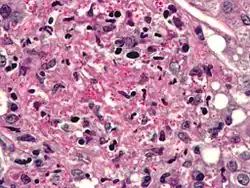

Cryptococcus

Cryptococcus neoformans can cause a severe form of meningitis and meningo-encephalitis in patients with HIV infection and AIDS. The majority of Cryptococcus species live in the soil and do not cause disease in humans. Cryptococcus neoformans is the major human and animal pathogen. Papiliotrema laurentii and Naganishia albida, both formerly referred to Cryptococcus, have been known to occasionally cause moderate-to-severe disease in human patients with compromised immunity. Cryptococcus gattii is endemic to tropical parts of the continent of Africa and Australia and can cause disease in non-immunocompromised people.[1]

Infecting C. neoformans cells are usually phagocytosed by alveolar macrophages in the lung.[11] The invading C. neoformans cells may be killed by the release of oxidative and nitrosative molecules by these macrophages.[12] However some C. neoformans cells may survive within the macrophages.[11] The ability of the pathogen to survive within the macrophages probably determines latency of the disease, dissemination and resistance to antifungal agents. In order to survive in the hostile intracellular environment of the macrophage, one of the responses of C. neoformans is to upregulate genes employed in responses to oxidative stress.[11]